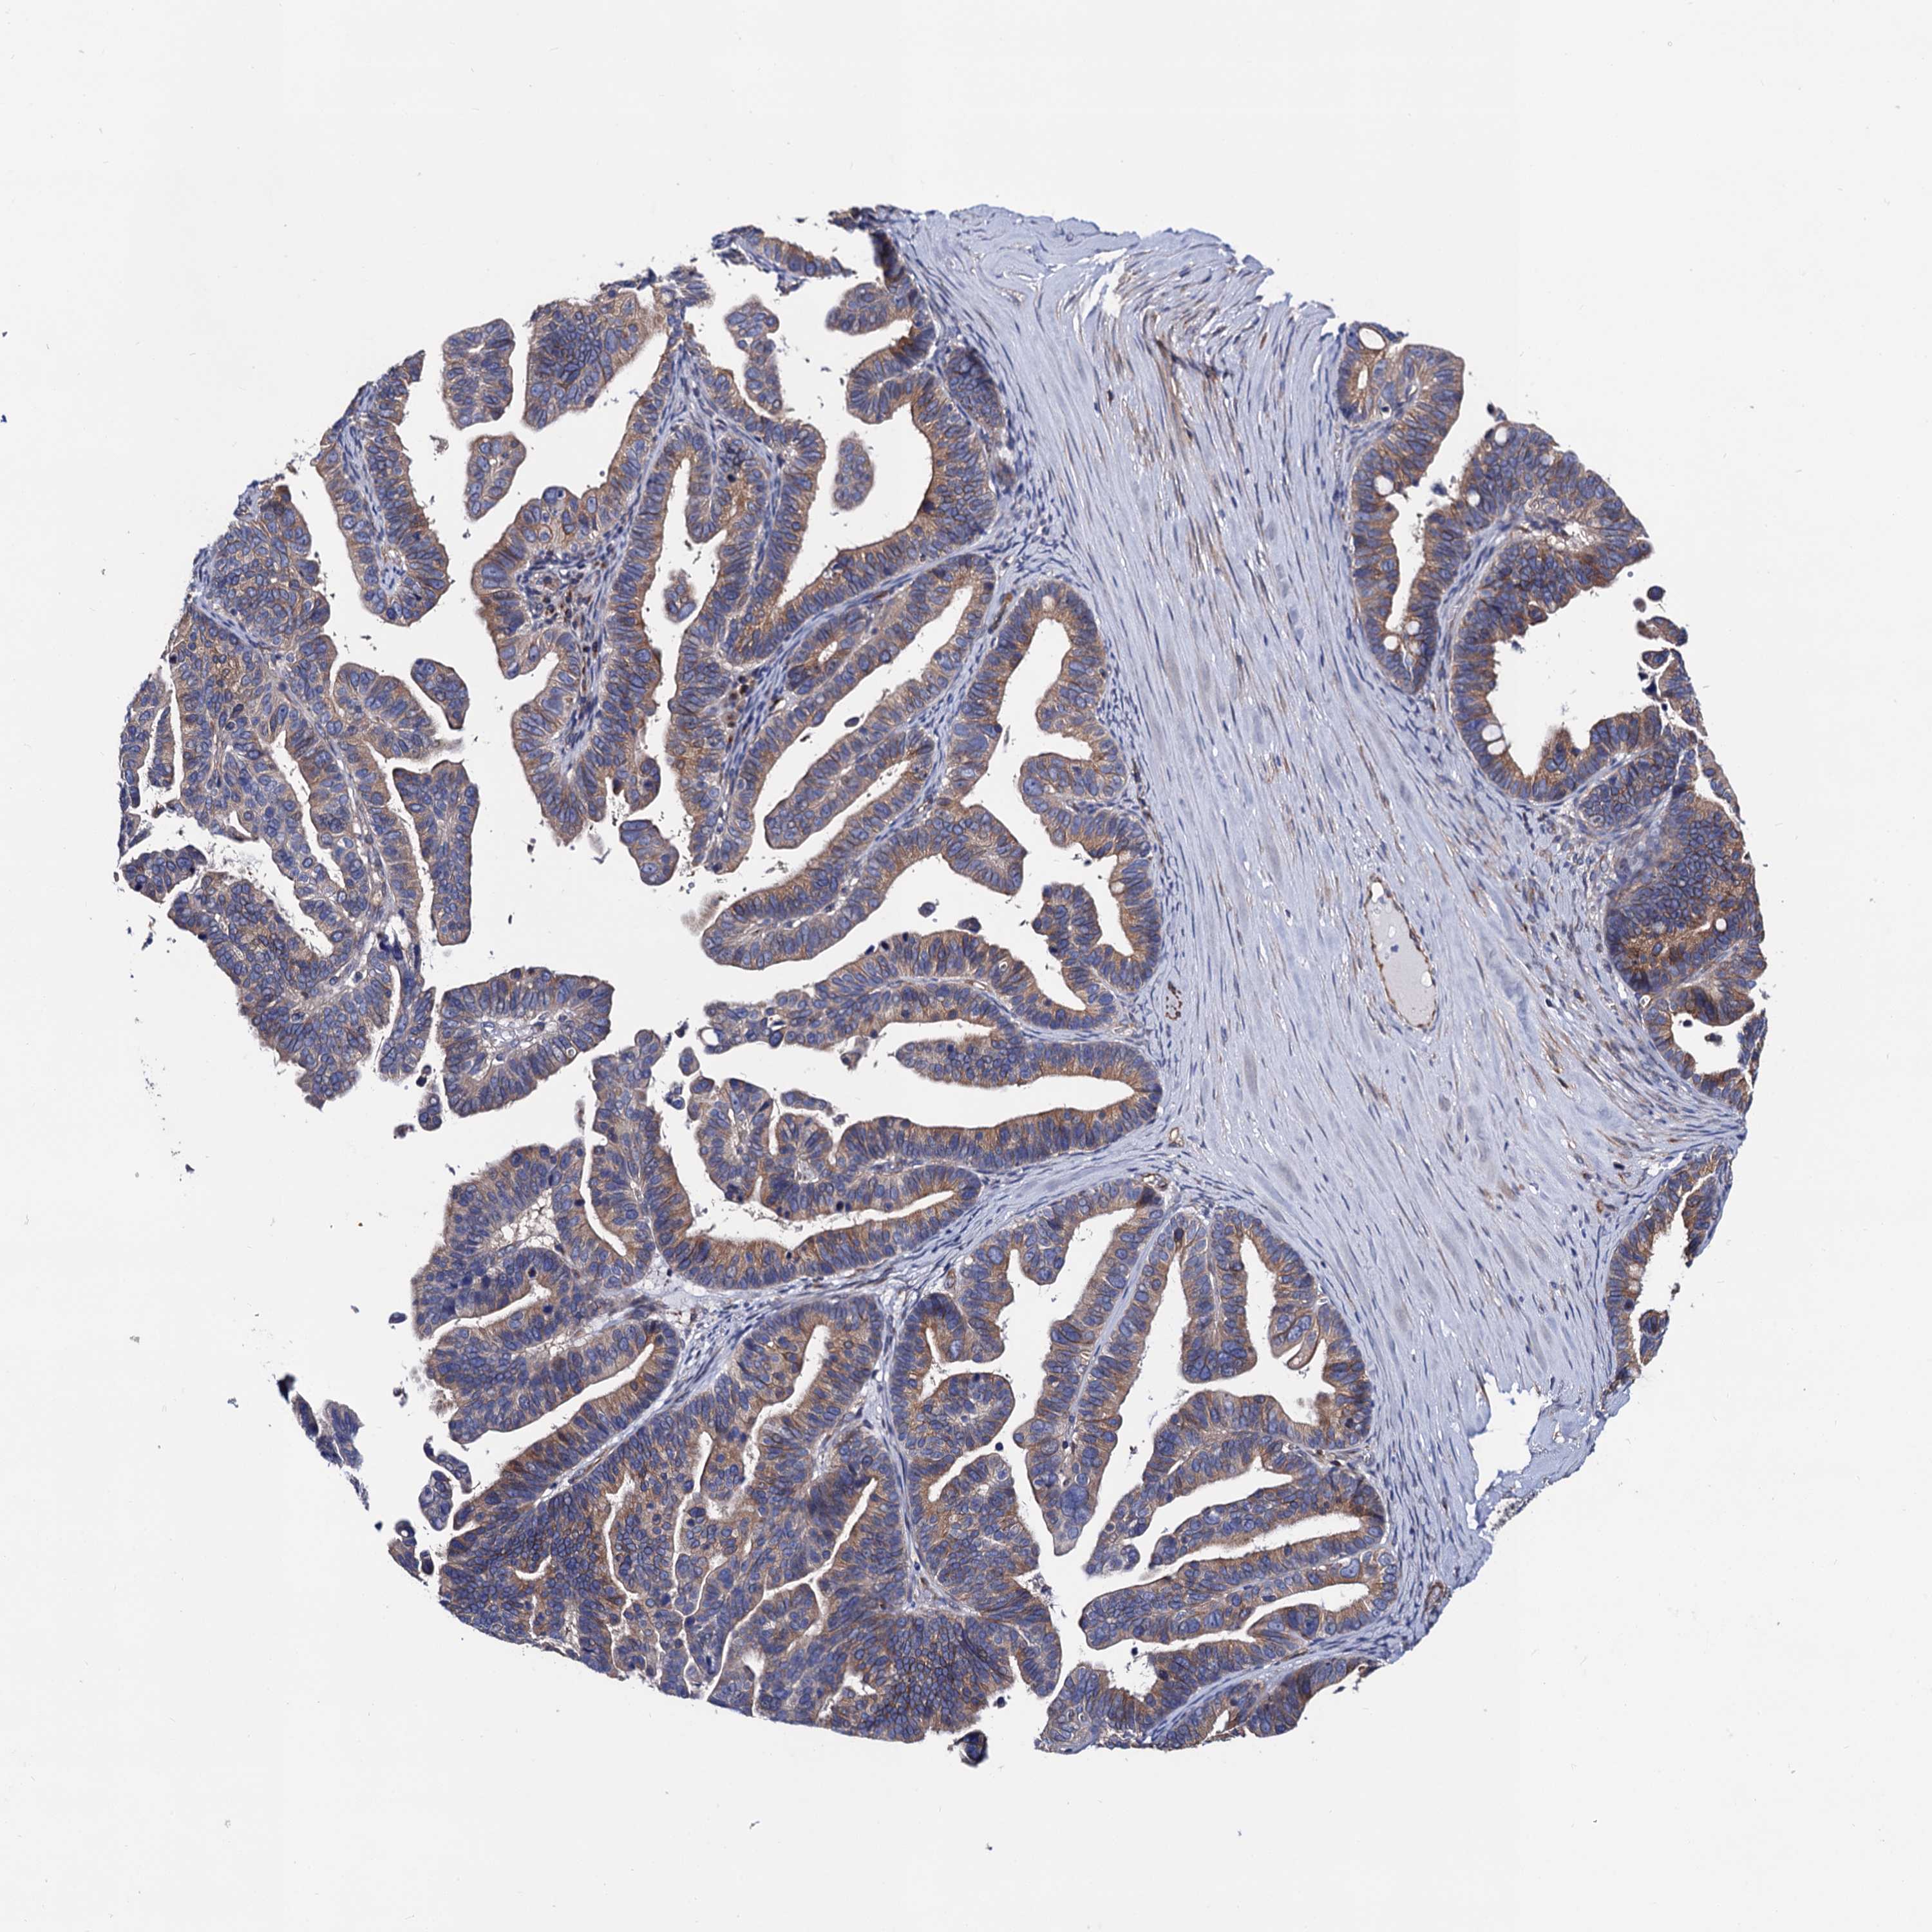

OVARIAN CANCER - Protein expressioni

A mouse-over function shows sample information and annotation data. Click on an image to view it in a full screen mode. Samples can be filtered based on level of antibody staining by selecting one or several of the following categories: high, medium, low and not detected. The assay and annotation is described here.

Note that samples used for immunohistochemistry by the Human Protein Atlas do not correspond to samples in the TCGA dataset.

Antibody stainingi

Antibody staining in the annotated cell types in the current human tissue is reported as not detected, low, medium, or high, based on conventional immunohistochemistry profiling in selected tissues. This score is based on the combination of the staining intensity and fraction of stained cells.

Each image is clickable and will lead to virtual microscopy that enables deeper exploration of all samples and also displays staining intensity scores, fraction scores and subcellular localization as well as patient and tissue information for each sample.

Antibody HPA040234

Staining

High

Medium

Low

Not detected

Intensity

Strong

Moderate

Weak

Negative

Quantity

>75%

75%-25%

<25%

None

Location

Nuclear

Cytoplasmic/membranous

Cytoplasmic/membranous,nuclear

Cystadenocarcinoma, serous, NOS

Carcinoma, endometroid

Cystadenocarcinoma, mucinous, NOS

Carcinoma, NOS